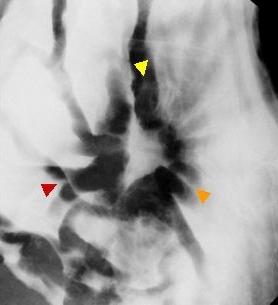

Criteria of Hist.ClassificationMalignant epithelial tumor/Adenocarcinoma

LocationStomach/Body

Technique, MethodX-ray

Macroscopic TypesType 3 Ulcerated type with infiltration/

Size30 - 34

Depth of Tumor Invasionserosa (adventitia)